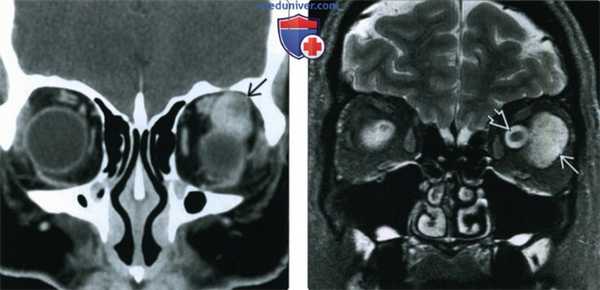

(Слева) При КТ с КУ в аксиальной проекции в правой глазнице в жировой клетчатке внутри мышечного конуса определяется овоидное контрастное объемное образование с четкими контурами, прилегающее к зрительному нерву и наружной прямой мышце.

(Справа) При МРТ Т1ВИ FS с КУ в аксиальной проекции наблюдается интенсивное контрастирование интраконального объемного образования. Образование имеет относительно небольшие размеры, оказывает незначительный эффект объемный эффект и не имеет агрессивных признаков. Такие образования зачастую существуют бессимптомно или вызывают постепенные изменения, не замечаемые пациентом.

(Слева) При КТ с КУ в корональной проекции внутри мышечного конуса определяется объемное образование; наблюдается раннее «лоскутное» контрастирование, что с высокой вероятностью указывает на кавернозную мальформацию глазницы. Хотя образование простирается к периферии глазницы, его центр лежит внутри мышечного конуса.

(Справа) При STIR MPT внутри мышечного конуса определяется крупная кавернозная мальформация. Образование дает интенсивный сигнал, аналогичный сигналу спинномозговой жидкости, окружающей смещенный зрительный нерв.